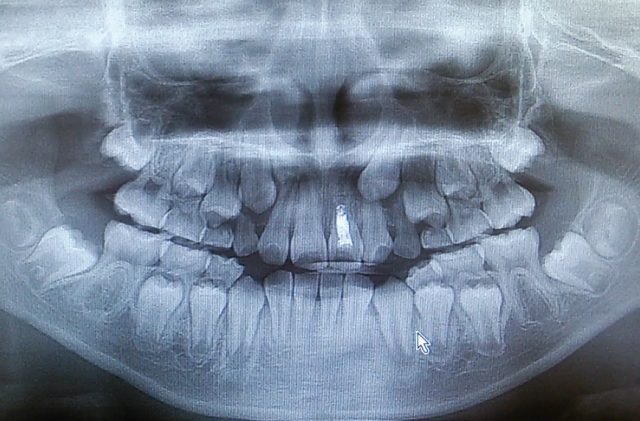

初めての歯科医院に行くと、お口のレントゲンを撮ることがあります。お口のレントゲンからどんなことがわかるのか、安全性は大丈夫なのかなど気にされる方もいらっしゃると思います。 今回はお口のレントゲンについて紹介いたします。